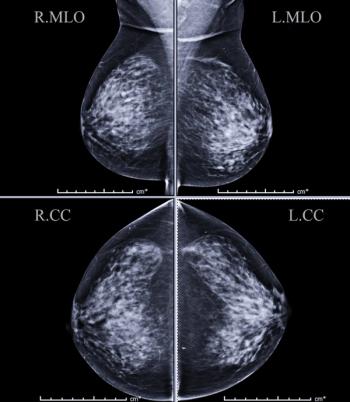

Combining DBT and synthetic mammography can mean less follow-up imaging for women with non-dense breasts – but not necessarily for women with dense tissue.

This AI tool is designed to work independently, dividing scans between those that need no radiologist assessment and those that require further interpretation.

Artificial intelligence algorithm can identify the same percentage of women with breast cancer as most radiologists.

Digital breast tomosynthesis improves cancer detection rates and reduces recalls, but not for all women.

Solution helps radiologists prioritize and identify suspicious mammograms.